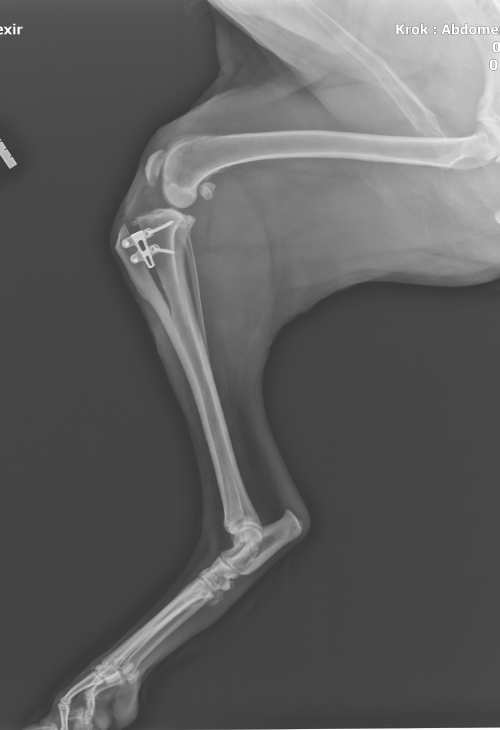

Obrázek 24:RTG snímek: výsledek operace TTA-Rapid, obrázek vlastní

Komplikace zde rozdělujeme na hlavní a vedlejší. Vedlejší komplikace jsou definovány jako komplikace, které nepotřebují chirurgický zákrok a zahojí se bez medikace. Dle studií se vyskytují do 18,4 % případů. Řadí se mezi ně právě i fraktura tibie (19).

Hlavní komplikace jsou definovány jako komplikace, které se je nutné vyřešit chirurgickým zásahem nebo pomocí medikace. Četnost hlavních komplikací se pohybuje do 15,1 % případů (19). I u této techniky, stejně jako u TPLO, se jako jedna z největších komplikací po operaci považuje infekce (19). Pokud se infekce znovu objeví i po ukončené antibiotické léčbě, je na zvážení chirurga, zda implantát neodstranit.

Výběr chirurgické metody je především na preferencích chirurga. Operace TTA Rapid má u určitých plemen a jedinců dobré výsledky a některé studie naznačují, že pomocí této techniky dojde k dřívějšímu zotavení a návratu mobility než pomocí operace TPLO (40).